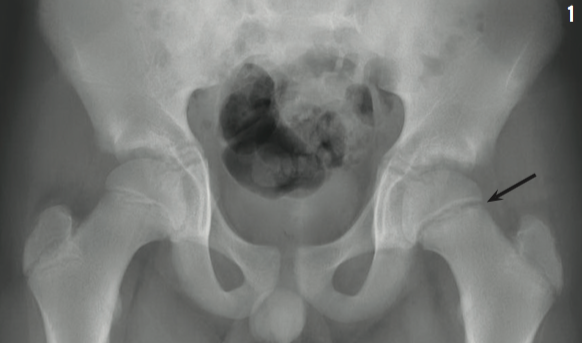

A 12-year-old boy presented to the orthopedic clinic with a 3-week history of left hip pain that began after he was tackled at a school football game. After the football injury, the boy was taken to an emergency facility where knee and hip radiographs were conducted, both with unremarkable results. He was given ibuprofen and crutches, discharged, and referred to an orthopedist. In the orthopedic clinic, he reported that 3 months prior to the football incident, he had noticed left knee pain for a few days, but the pain had since resolved. However, he denied having fever or pain in other joints at the present time. His physical examination results were notable for a weight of 55.8 kg (90th percentile), a body mass index of 26.6 (97th percentile), and external rotation of the left leg while supine. When the boy stood on the affected leg, the gluteal fold on the unaffected side fell instead of rising, indicating a positive Trendelenburg sign. An anteroposterior (AP) radiograph of the boy’s hip was obtained (Figure 1).

Hip pain in children can indicate a variety of possible diagnoses (Table).1-3 In our patient, the AP radiograph of the hip showed a Type 1 Salter-Harris fracture, or slipped capital femoral epiphysis (SCFE), of the left physis. The boy underwent surgical pinning of the affected and unaffected hips the next day (Figure 2).

Seventy-five percent of SCFEs are unilateral. Hip pain and limping are common, but pain in the knee or groin can also occur. At rest, hip flexion and external rotation are favored due to the new anatomic geometry formed by the slip.5,6 The frog-leg lateral radiograph best shows the posterior slippage, and the AP view shows widening of the growth plate and rarefaction of the adjacent metaphysis.4,7